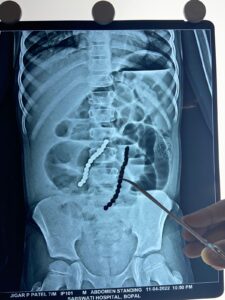

પરિવારજનો ચિંતાતુર બનતા સિવિલ હોસ્પિટલના બાળરોગ સર્જરી વિભાગમાં આવી પહોચ્યા. અહીના તબીબોએ બાળકનો એક્સ-રે અને સી.ટી. સ્કેન કરીને નિદાન કરતા જ્ઞાત થયું કે, બાળકના પેટમાં જુદા-જુદા ૧૪ મણકા છે. જે હોજરી પછી આવેલા નાના આંતરડા સુધી પહોંચ્યા છે.

સિવિલ હોસ્પિટલના સુપ્રીટેન્ડન્ટ અને બાળરોગ સર્જરી વિભાગના વડા ડૉ.રાકેશ જોષી અને તેમની ટીમ દ્વારા બાળકની સર્જરી હાથ ધરવામાં આવી. સર્જરી દરમિયાન માલુમ પડ્યું કે શરીરમાં રહેલા ૧૪ મણકા આંતરિક આકર્ષણના કારણે ઘર્ષણ ઉત્પન્ન કરી રહ્યા હતા અને આંતરડામાં ૭ કાણા પાડ્યા હતા. જેના પરથી જ માલૂમ પડે કે સર્જરી કેટલી જટીલ અને જોખમી રહી હશે.

આ સર્જરીની જટીલતા વર્ણવતા ડૉ.જોષી કહે છે કે, નાના બાળકમાં હોજરીની ખૂબ જ નજીક આંતરડાનું સ્થાન હોય છે. જેથી આ અંતર ખૂબ જ ઓછુ હોવાથી ઓપરેશનનું રિસ્ક તેટલું જ વધુ થઇ જાય છે. આંતરડામાં જુદી જુદી જગ્યાએ ચોંટેલા ૧૪ ચુંબકીય મણકાએ આંતરડાની દિવાલમાં અનેક કાણાં પાડ્યા હતા. જેથી આ સર્જરી કરીને તમામ ટુકડાઓને એકસાથે કાઢવા જરૂરી હતા. જેથી સર્જરી વખતે ૧૪ ચુંબકીય મણકાને બહાર કાઢવા માટે બે જગ્યાએ આંતરડામાં કાંપ મૂકીને બહાર કાઢ્યા બાદ ટાંકા લેવા પડ્યા છે.સિવિલ હોસ્પિટલના બાળરોગ સર્જરી વિભાગની ડૉ. જોષી અને ડૉ. અઝીઝ રત્નાની તેમજ એનેસ્થેસિયા વિભાગના ડૉ. સીમા ગાંધી અને તેમની ટીમની કોઠાસુઝના પરિણામે ઓપરેશનને સરળતાથી પાર પાડી શકાયું.